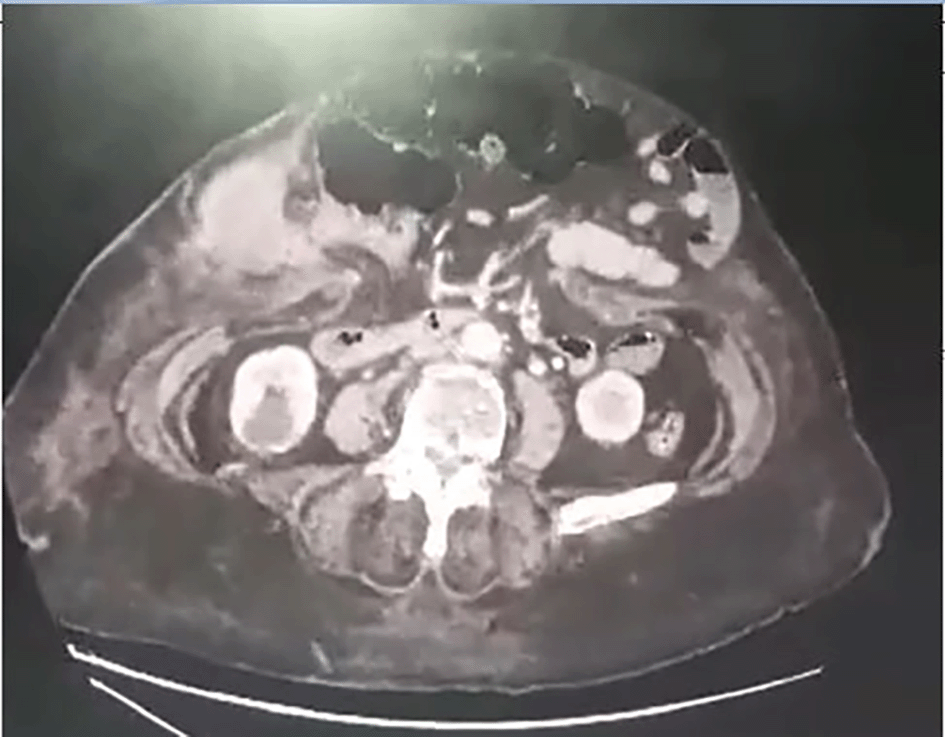

An 81-year-old woman with a history of diabetes mellitus, hypertension, arterial fibrillation, and ventral hernia repair was scheduled to undergo surgery for a recurrent hernia. She consulted an emergency department for rapidly increasing abdominal pain for 6 days. Upon examination, the umbilicus bulged with overlying sphacelous skin (Figure 1). Biology was as following: CRP = 167.3 mg/L, WBC = 12020/mm3, creatinine = 121.84 μmol/L, urea 9 mmol/L, hemoglobin = 12.3 g/dL. An abdominal CT scan revealed a herniated right colon through a 25 mm defect, an enlarged appendix measuring 18 mm, and communication with a 5 cm intrasaccular abscess (Figure 2). She then rushed to the operating theater. Upon incision, pus was evacuated from the hernial sac. The right colon was incarcerated within the aponeurotic defect, with no signs of digestive distress, and the peritoneal cavity was not contaminated due to the constriction ring at the neck of the sac. The appendix was gangrenous with a perforated tip eliciting mucus (Figure 3). Thorough lavage with appendicectomy and herniorrhaphy was performed. She died on 5th postoperative day to a pulmonary oedema. Histological analysis revealed a well-differentiated adenocarcinoma that developed within a serrated adenoma (Figure 4). It was classified pT3. Mucus was acellular (Figure 5). The hernial sac harbors similar cancerous cells.